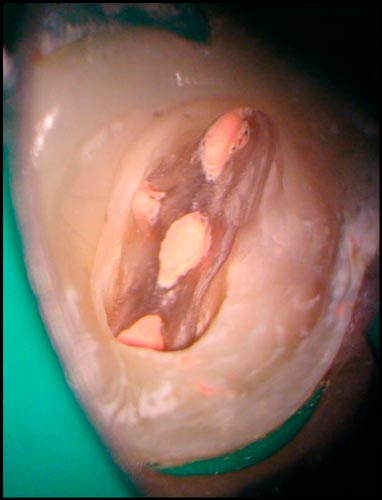

"Підступний" МВ2

Підступний" МВ2

1) Частота поширення та найбільш поширені варіанти анатомії. Особливості анатомії відносно інших каналів.

2) Правила пошуку. Секрети, лайфхаки та як не зробити "діагностичну" перфорацію.

3) Визначення робочої довжини та інструментація в залежності від складності: від скаутингу до повного проходження.

4) Обтурація МВ2 в залежності від складності анатомії, чи завжди це можливо? Що буде, якщо пропустити МВ2?

5) Менеджмент проблем та ускладнень на різних етапах. Розбір клінічних кейсів.